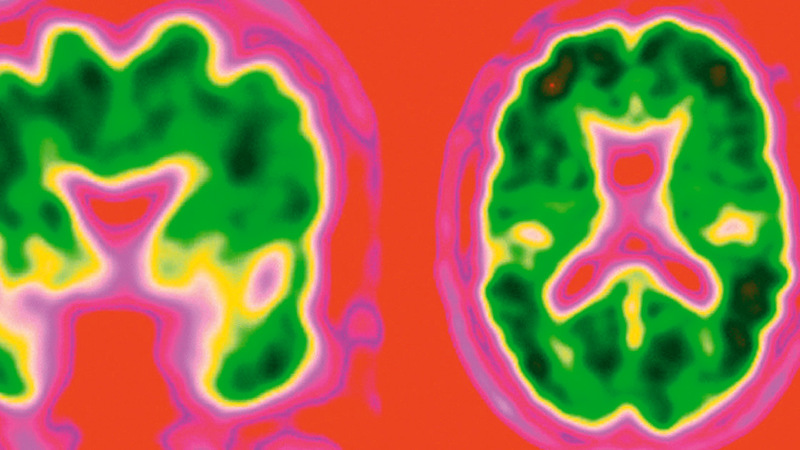

الاختبار يقيس مستويات بروتين عثر عليه العلماء في أدمغة المصابين بالزهايمر. من المصدر

ويقيس اختبار الدم الجديد مستويات بروتين بيتا أميلويد، وهو البروتين الذي عثر عليه العلماء في أدمغة المصابين بمرض الزهايمر، ويستخدم حالياً التصوير المقطعي بالإصدار البوزيتروني لاختبار وجود البروتين بأدمغة المشاركين في الدراسات، لكنه مكلف جداً.